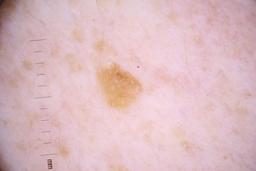

ISIC_4077341

Clinical

| Field | Value |

|---|---|

| acquisition_day | 1 |

| age_approx | 50 |

| anatom_site_1 | Trunk |

| anatom_site_2 | Anterior trunk |

| concomitant_biopsy | False |

| dermoscopic_type | contact non-polarized |

| diagnosis_1 | Benign |

| diagnosis_confirm_type | serial imaging showing no change |

| family_hx_mm | False |

| image_type | dermoscopic |

| lesion_id | IL_9238622 |

| patient_id | IP_1969685 |

| personal_hx_mm | True |

| sex | male |